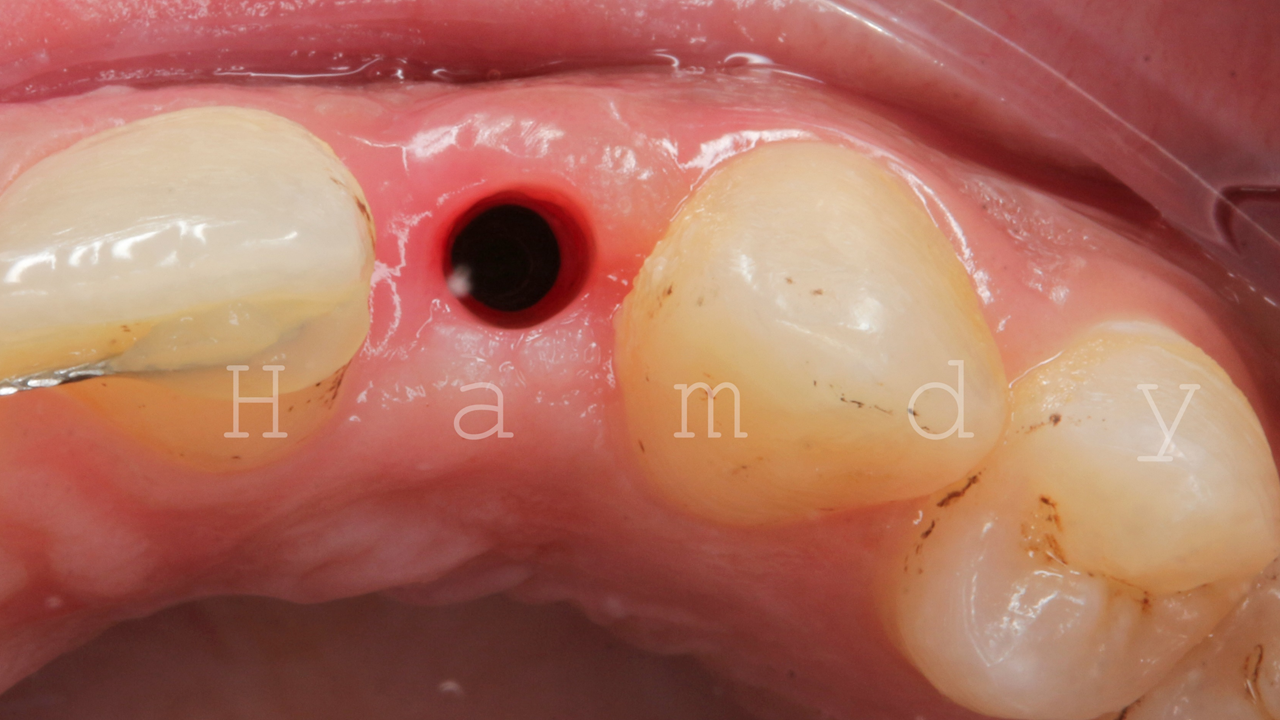

![]() |

as we noticed in this case the ready made healing abutment couldn't support perfectly neither the labial